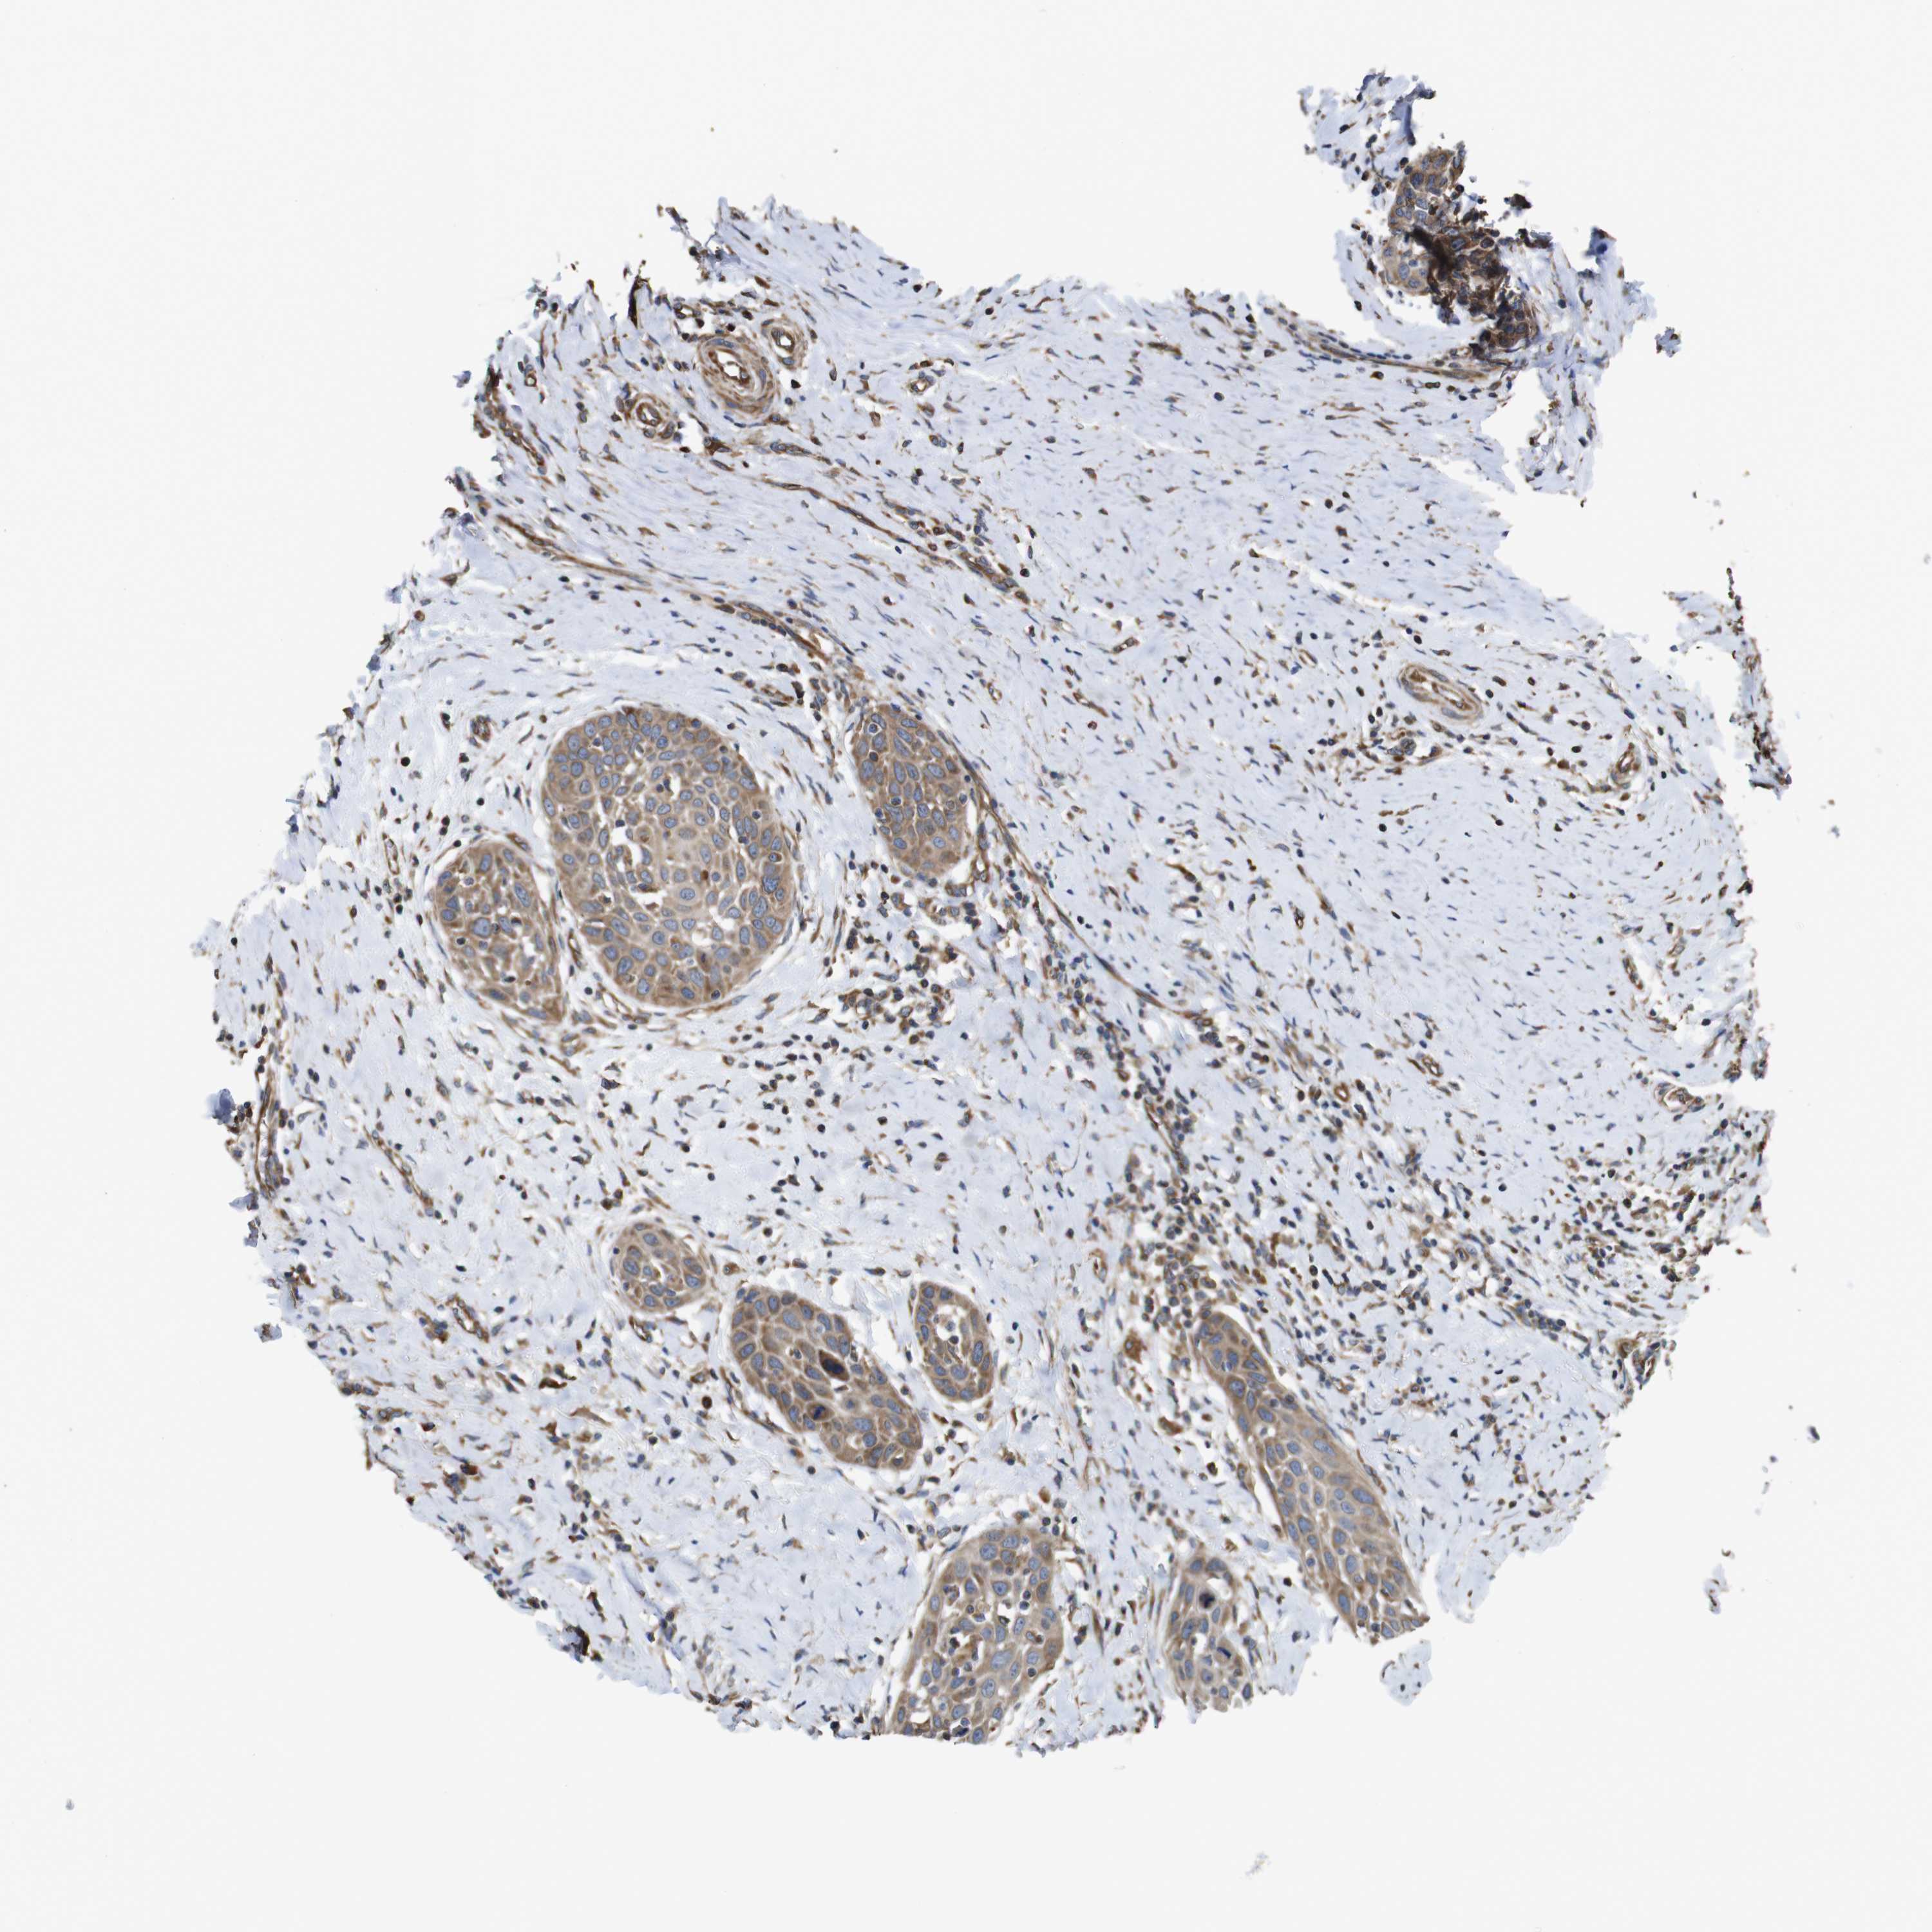

HEAD AND NECK CANCER - Protein expressioni

A mouse-over function shows sample information and annotation data. Click on an image to view it in a full screen mode. Samples can be filtered based on level of antibody staining by selecting one or several of the following categories: high, medium, low and not detected. The assay and annotation is described here.

Antibody stainingi

Antibody staining in the annotated cell types in the current human tissue is reported as not detected, low, medium, or high, based on conventional immunohistochemistry profiling in selected tissues. This score is based on the combination of the staining intensity and fraction of stained cells.

Each image is clickable and will lead to virtual microscopy that enables deeper exploration of all samples and also displays staining intensity scores, fraction scores and subcellular localization as well as patient and tissue information for each sample.

Antibody HPA013321

Staining

High

Medium

Low

Not detected

Intensity

Strong

Moderate

Weak

Negative

Quantity

>75%

75%-25%

<25%

None

Location

Nuclear

Cytoplasmic/membranous

Cytoplasmic/membranous,nuclear

Squamous cell carcinoma, NOS